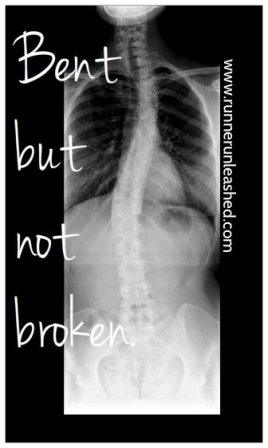

I’ve spent lots of time in hospital beds, physical therapy offices, and on the operating table. Mistakes, accidents, and trauma have left me with chronic back pain and chronic headaches from my Scoliosis. My spine is still very curved, as you can see in the photo, my left side sticks out, and I have a little dimple of space in the bottom. My right shoulder is a lot lower and makes many normal positions such as standing uncomfortable. On top of it, I have severe muscles damage, since to get to my spine they had to cut through the muscles. I actually have no feeling in my right shoulder =( It’s very painful and it’s always present and swollen as shown.

I am not a fast runner, and I do need time to catch my breath since there is limited space in my lungs. My breaths are loud and sounds like I am running too fast for what I can handle but that is not the case, I don’t have the space to breath. I can run long distances with the beginning being the hardest. Once I find my rhythm there is no stopping me. I do get shin splints, back pains, and PF pain but I have learned many ways to keep them under control which I have shared with you all =)